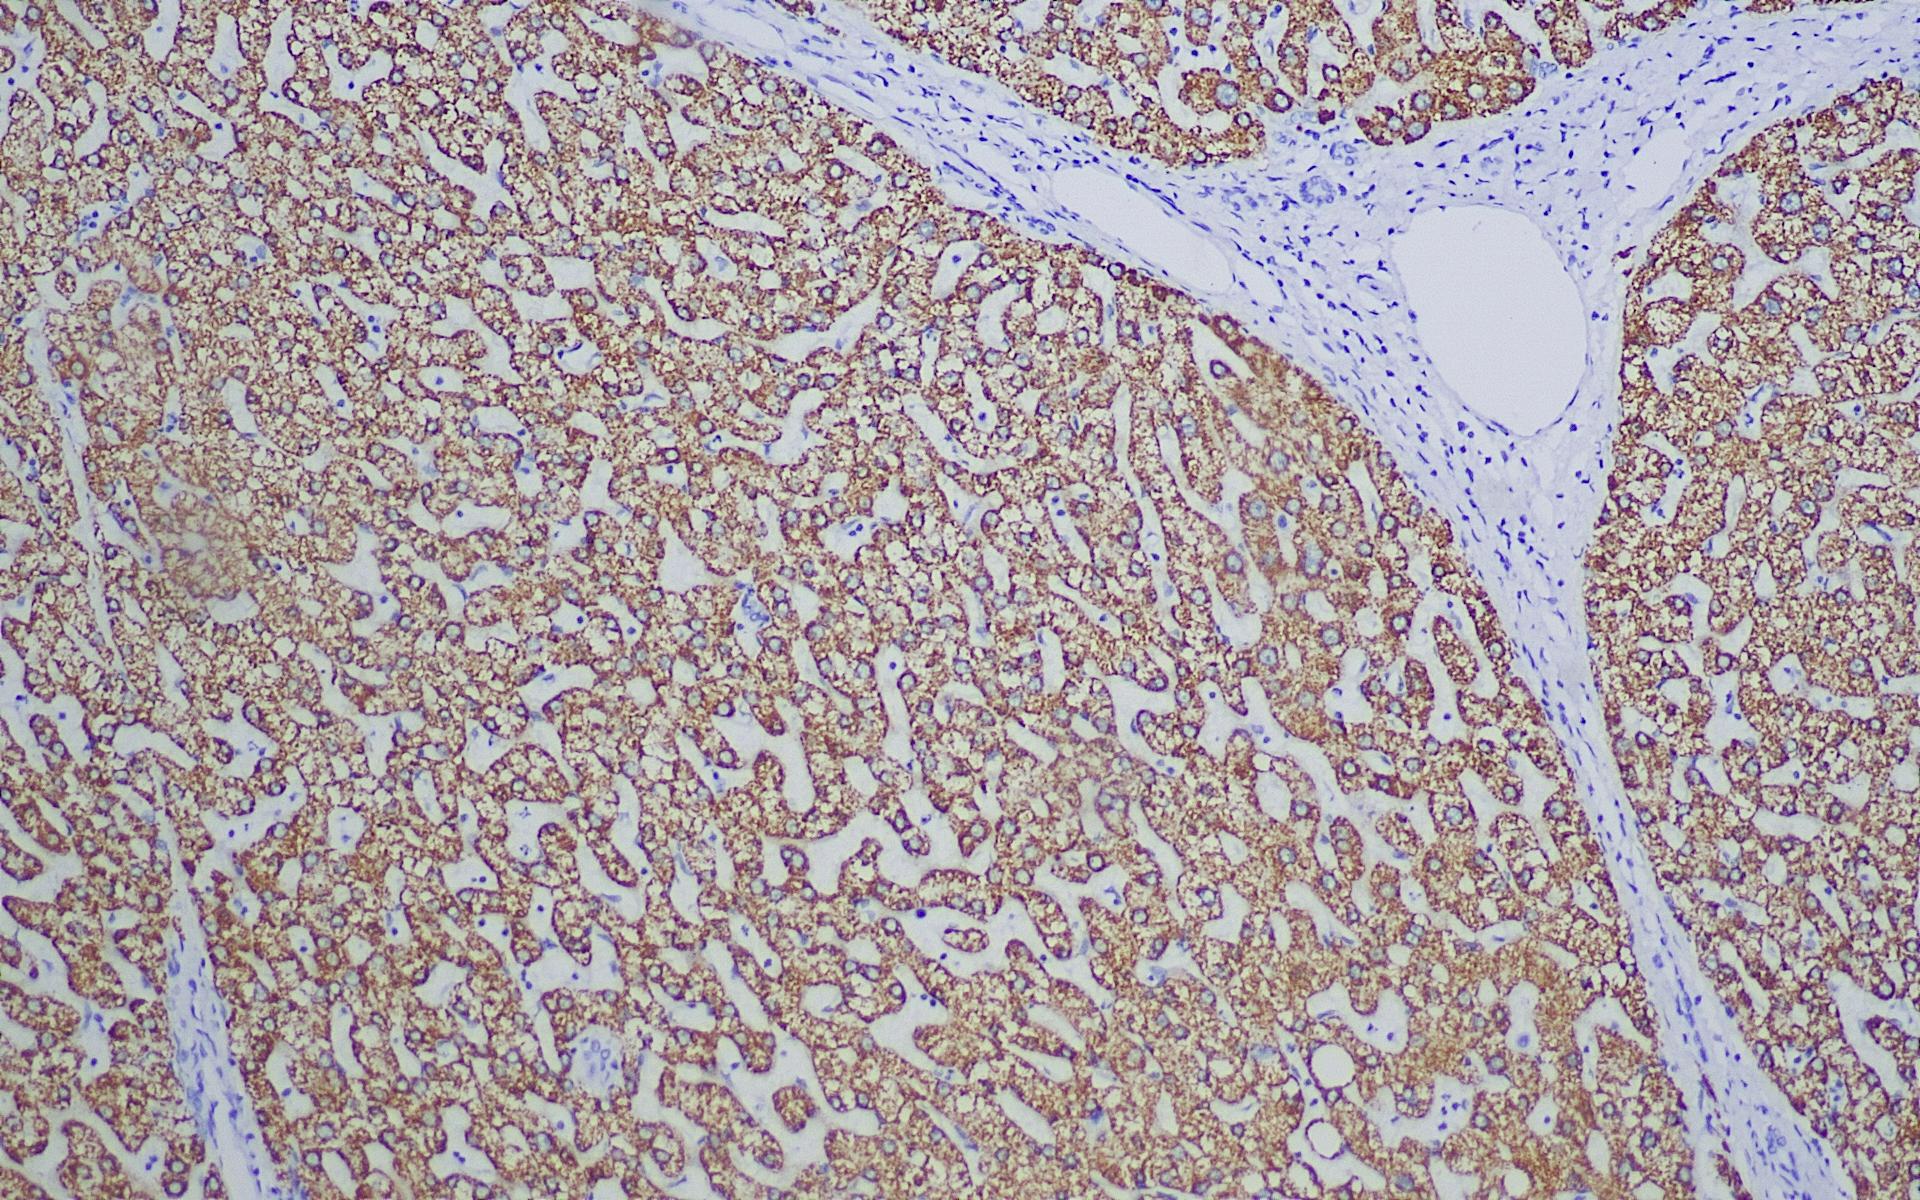

Hepatocyte Specific Antigen

此抗体识别的抗原存在于正常人肝细胞和大多数的肝细胞癌中,与许多其它人类肿瘤包括消化道肿瘤细胞没有反应。此抗体可以对绝大多数的肝细胞癌进行染色,主要用于肝肿瘤的研究。

HSA肝脏